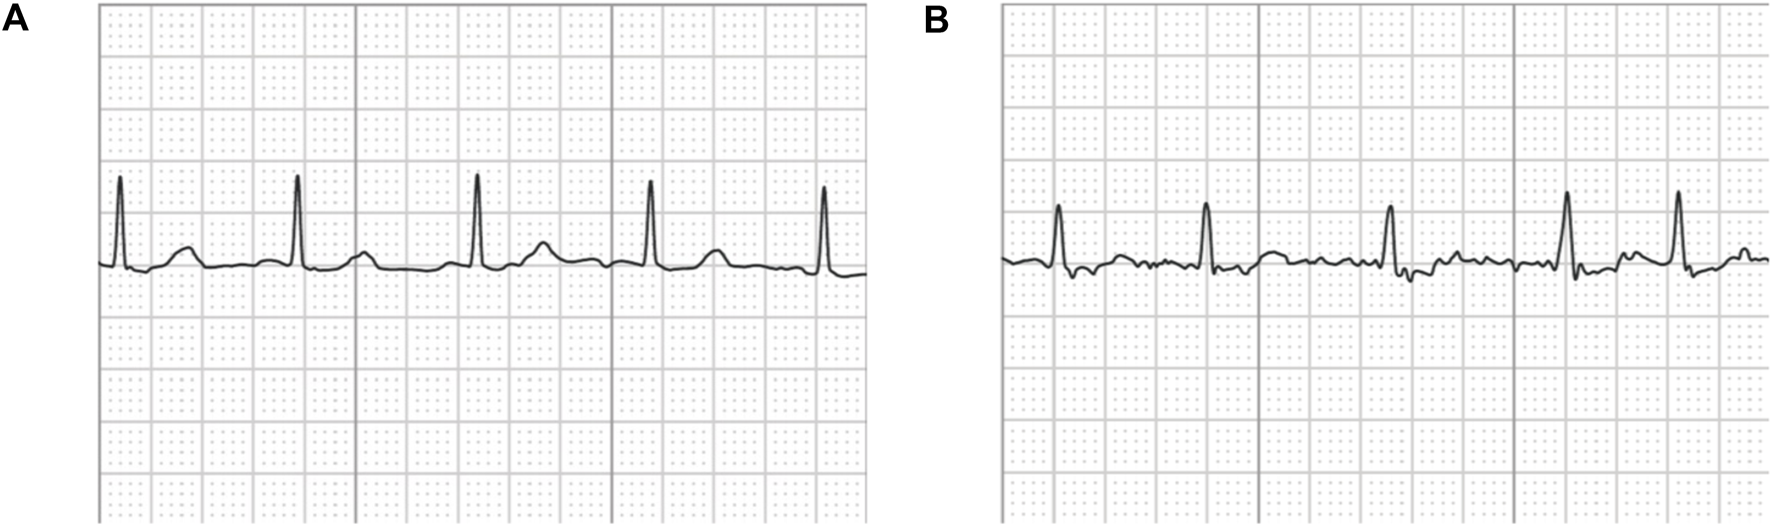

Note that the original ECG recordings from OUHSC are in PDF format, as shown in Figure 1A. It is necessary to accurately extract the numerical ECG readings from the PDF files for further data preprocessing and analysis, which is achieved by the following procedure:

Transforming PDF files into gray-scale images represented by 2D-pixel matrices: We discretize the 2D image into a pixel matrix. Then, each pixel is converted to a fixed number of bits to represent the gray-scale intensity of the corresponding point in the image. As shown in Figure 1A, the ECG signals are displayed in the darkest color on the plot with the color intensity of 1, i.e., h(m, n) = 1, while the grid lines appear in a lighter color, i.e., 0 < h(m, n) < 1, where h(m, n) denotes the color intensity of the pixel at column m and row n. Note that the background color intensity is 0.

Removing grid lines from the ECG plot: We replace the pixel shade values of the grid lines with the background color value: i.e., h(m, nh(m, n) < 1) = 0. This allows the ECG signals to distinguishably stand out, as illustrated in Figure 1B. The quantized image is thus encoded into a binary digital format, i.e., black as “1” and white as “0”. As such, the entire ECG image is transformed into a binary digital matrix without the grid lines.

Figure 1. An example of (A) a raw image recording of an ECG segment in PDF format, (B) the ECG image that filters out the grid background, (C) the digitalized ECG time series signal.